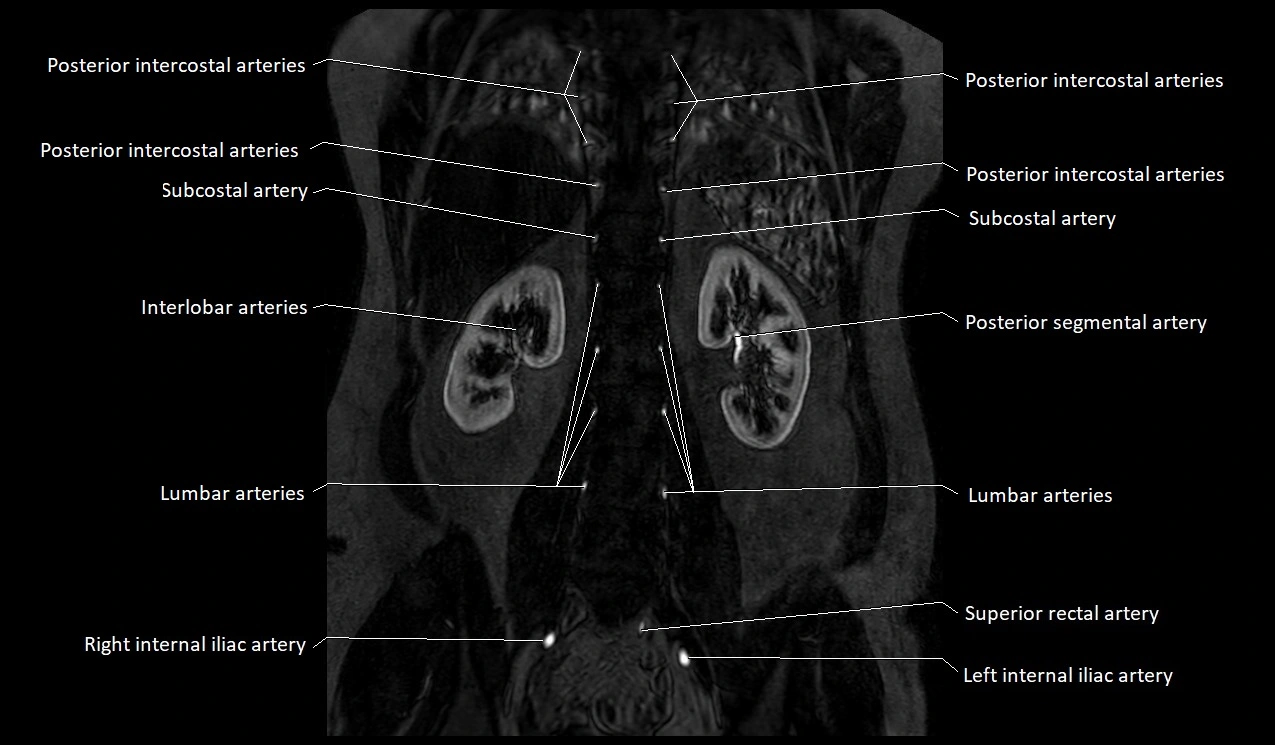

MRI Appearance

T1-weighted images:

Artery appears as a small linear hypointense flow void coursing over the superior pubic ramus

Seen within bright perivascular fat of pelvis

T2-weighted images:

Artery lumen is a signal void

In thrombosed or diseased variants, lumen may appear hyperintense relative to surrounding fat

STIR:

Fat suppression makes the artery more visible within pelvic fat

Helps identify perivascular edema, hematoma, or inflammatory changes

T1 Post-Gadolinium (with fat suppression):

Artery enhances brightly and homogeneously

Useful for tracing the course, anastomoses, and presence of corona mortis

Highlights arterial wall thickening or tumor encasement if present

MRA Pelvis with Gadolinium:

Clearly delineates the origin, course, and anastomoses of the accessory obturator artery

Identifies connection with inferior epigastric artery, external iliac artery, or obturator artery

Excellent for detecting vascular variants prior to surgery

Useful in mapping pelvic vasculature in trauma, tumor embolization, or preoperative planning